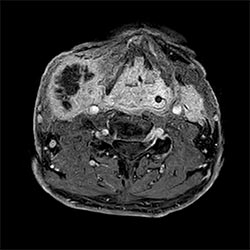

Breast